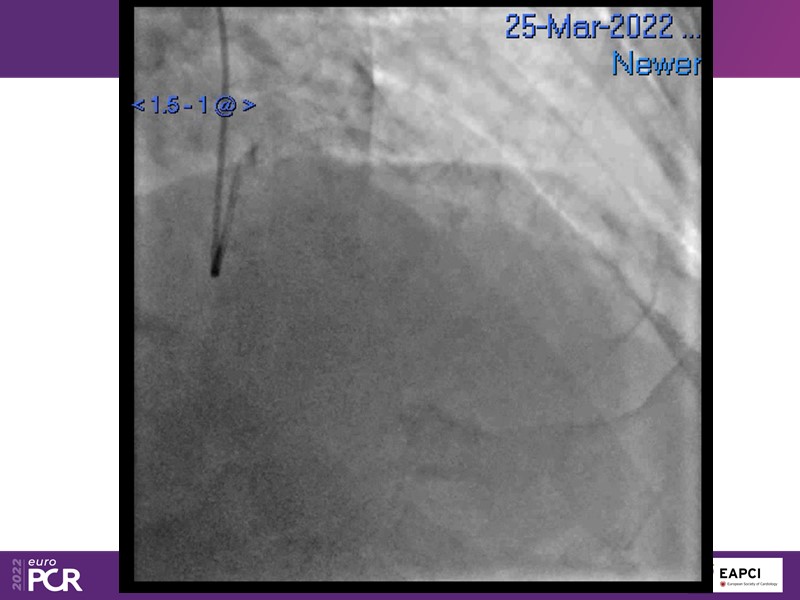

Alexandre Abizaid, Marco Valgimigli, Fazila Malik, Luca Testa, Patrick W. Serruys, Damiano Regazzoli, Kumar Prathap, and Sandeep Basavarajaiah take turns in this session to discuss two innovative technologies: a stent platform with nanotechnology and a novel drug-coated balloon (DCB). These novel technologies both have unique features that could change daily practice and improve outcomes.

- To find out more about the application and mechanism of a sirolimus coated balloon for coronary artery disease treatment with case presentations in complex settings